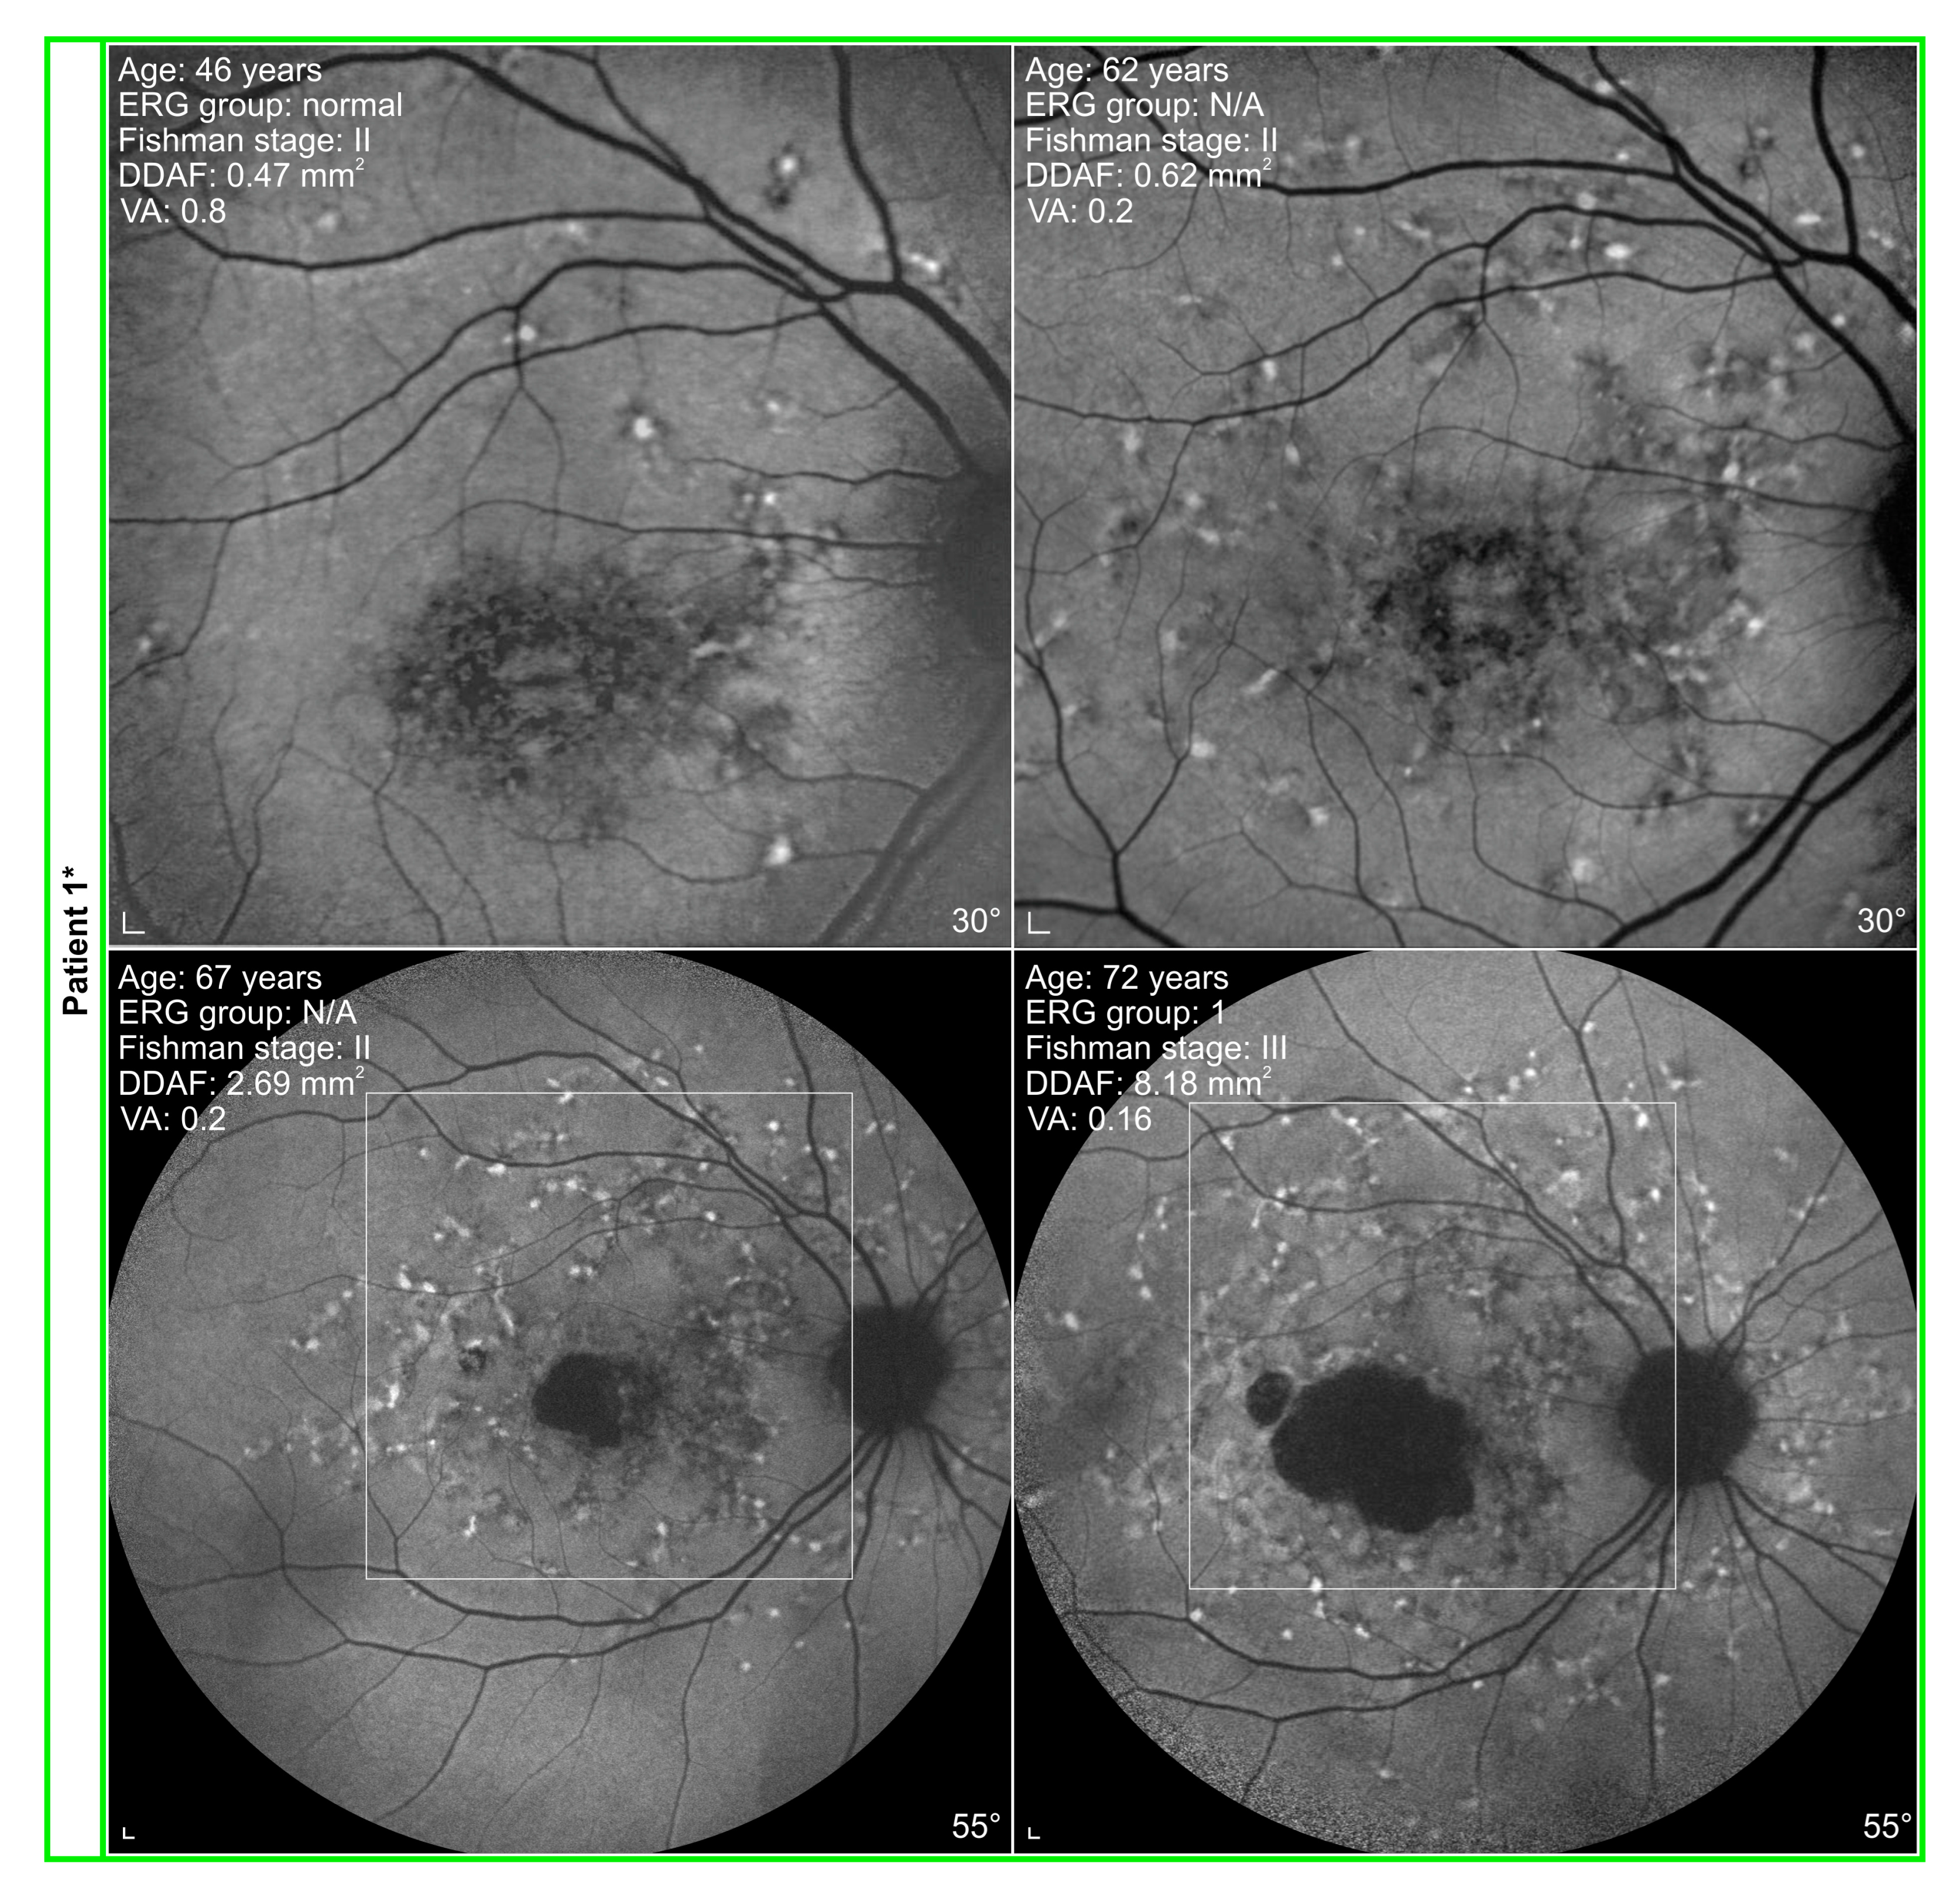

3.2. Electrophysiological and Fundus Autofluorescence Progression